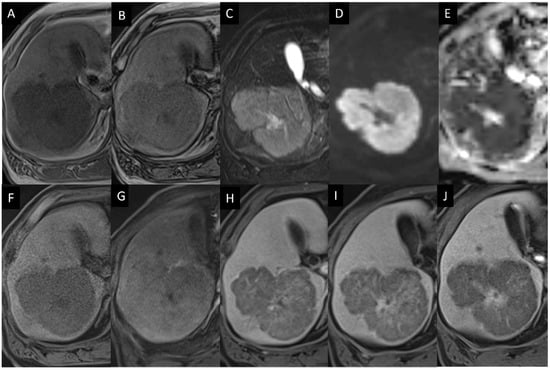

- Colagrande, S.; Calistri, L.; Grazzini, G.; Nardi, C.; Busoni, S.; Morana, G.; Grazioli, L. MRI features of primary hepatic lymphoma. Abdom. Radiol. 2018, 43, 2277–2287. [Google Scholar] [CrossRef]